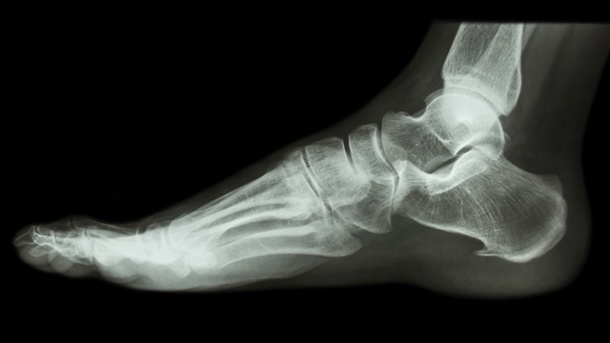

Fuss & Sprunggelenk

Behandlungen von Fuss- und Sprunggelenksleiden sind unser Kerngebiet, so zum Beispiel Operationen bei immer wieder auftretenden Verstauchungen mit Instabilitäten des Sprunggelenkes, Achillessehnenverletzungen, Knöchelbrüche, Sportverletzungen, und Fussdeformitäten wie Hallux valgus, Spreizfüsse, angeborene Fehlstellungen, Hammerzehen. Die Entwicklungen auf diesem Fachgebiet sind enorm vorangeschritten, sodass heute viele Eingriffe in entsprechender arthroskopischer oder minimal-invasiver Technik durchgeführt werden können. Dies führt in der Regel zu bedeutend kürzeren Spitalaufenthalten.